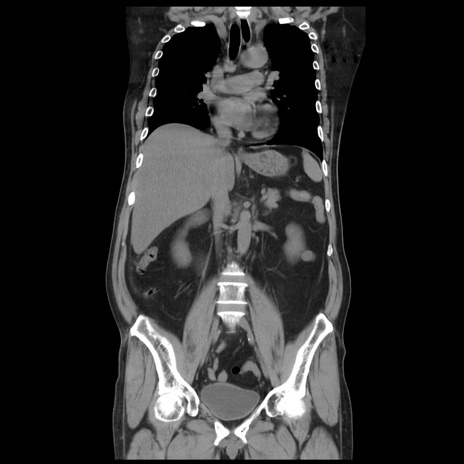

症例20(冠状断像)

【症例】 60歳代男性

【主訴】 腹部膨満、嘔吐

【現病歴】5日前頃より倦怠感を認め食事量減少し4日前の朝嘔吐、食事摂取困難となった。 3日前近医受診し点滴施行され整腸剤などを処方された。 当日他院を受診し、腹部膨満著明、炎症反応の上昇(CRP10.8、WBC11200)あり、紹介受診となる。

【身体所見】 意識JCS1 受け答えがはっきりしないBP 111/57mHg、 P 67bpm、、BT35.2°C、SpO2 97%(RA)、 腹部:膨隆、打診で鼓音あり、全体的に圧痛有り、腸蠕動音(-)、反跳痛ははっきりせず。

【データ】WBC 11400、CRP 14.20